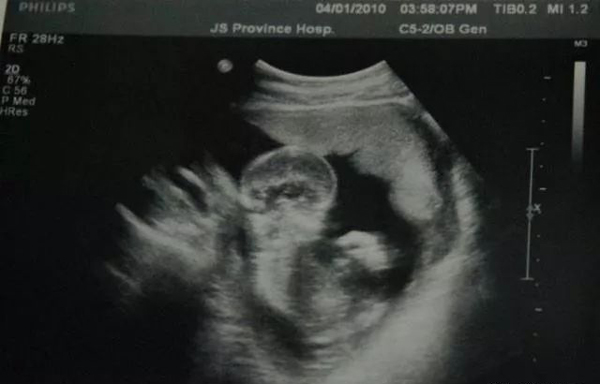

بوۋاقلار تۇغۇلۇشتىن بۇرۇن، ھامىلدار ئايالنىڭ قوسىقىدا باش سۈيى ئىچىدە تۇرىدىغان بولۇپ، باش سۈيىنىڭ سۈپىتى ھامىيلىنىڭ ساغلاملىقىغا ئىنتايىن مۇھىم تەسىر كۆرسىتىدۇ. ئەگەر ھامىلدار ئايالنىڭ باش سۈيى ئازلاپ كەتسە، ھامىيلىگە ئوكسىگىن يىتىشمەسلىكنى كەلتۈرپ چىقىرىشى مۇمكىن؛ بۇنىڭ بىلەن بىرگە، باش سۈيىنىڭ پاكىزە بولۇش بولماسلىقىمۇ، ھامىيلىنىڭ ساغلاملىقىغا چوڭ تەسىر كۆرسىتىدۇ.

ھامىلدارلىق مەزگىلىدە، ھامىلدار ئايالنىڭ تۇرمۇش ئادىتىنىڭ، باش سۈيىنىڭ سۈپىتىگە تەسىر يەتكۈزۈش ئىھتىماللىقى بار بولۇپ، تۆۋەندىكى نەچچە خىل ناچار ئادەتلەر، باش سۈيىنىڭ سۈپىتىنى تۆۋەنلىتىۋىتىپ، ھامىيلىنىڭ نورمال يىتىلىشىگە تەسىر كۆرسىتىدۇ.